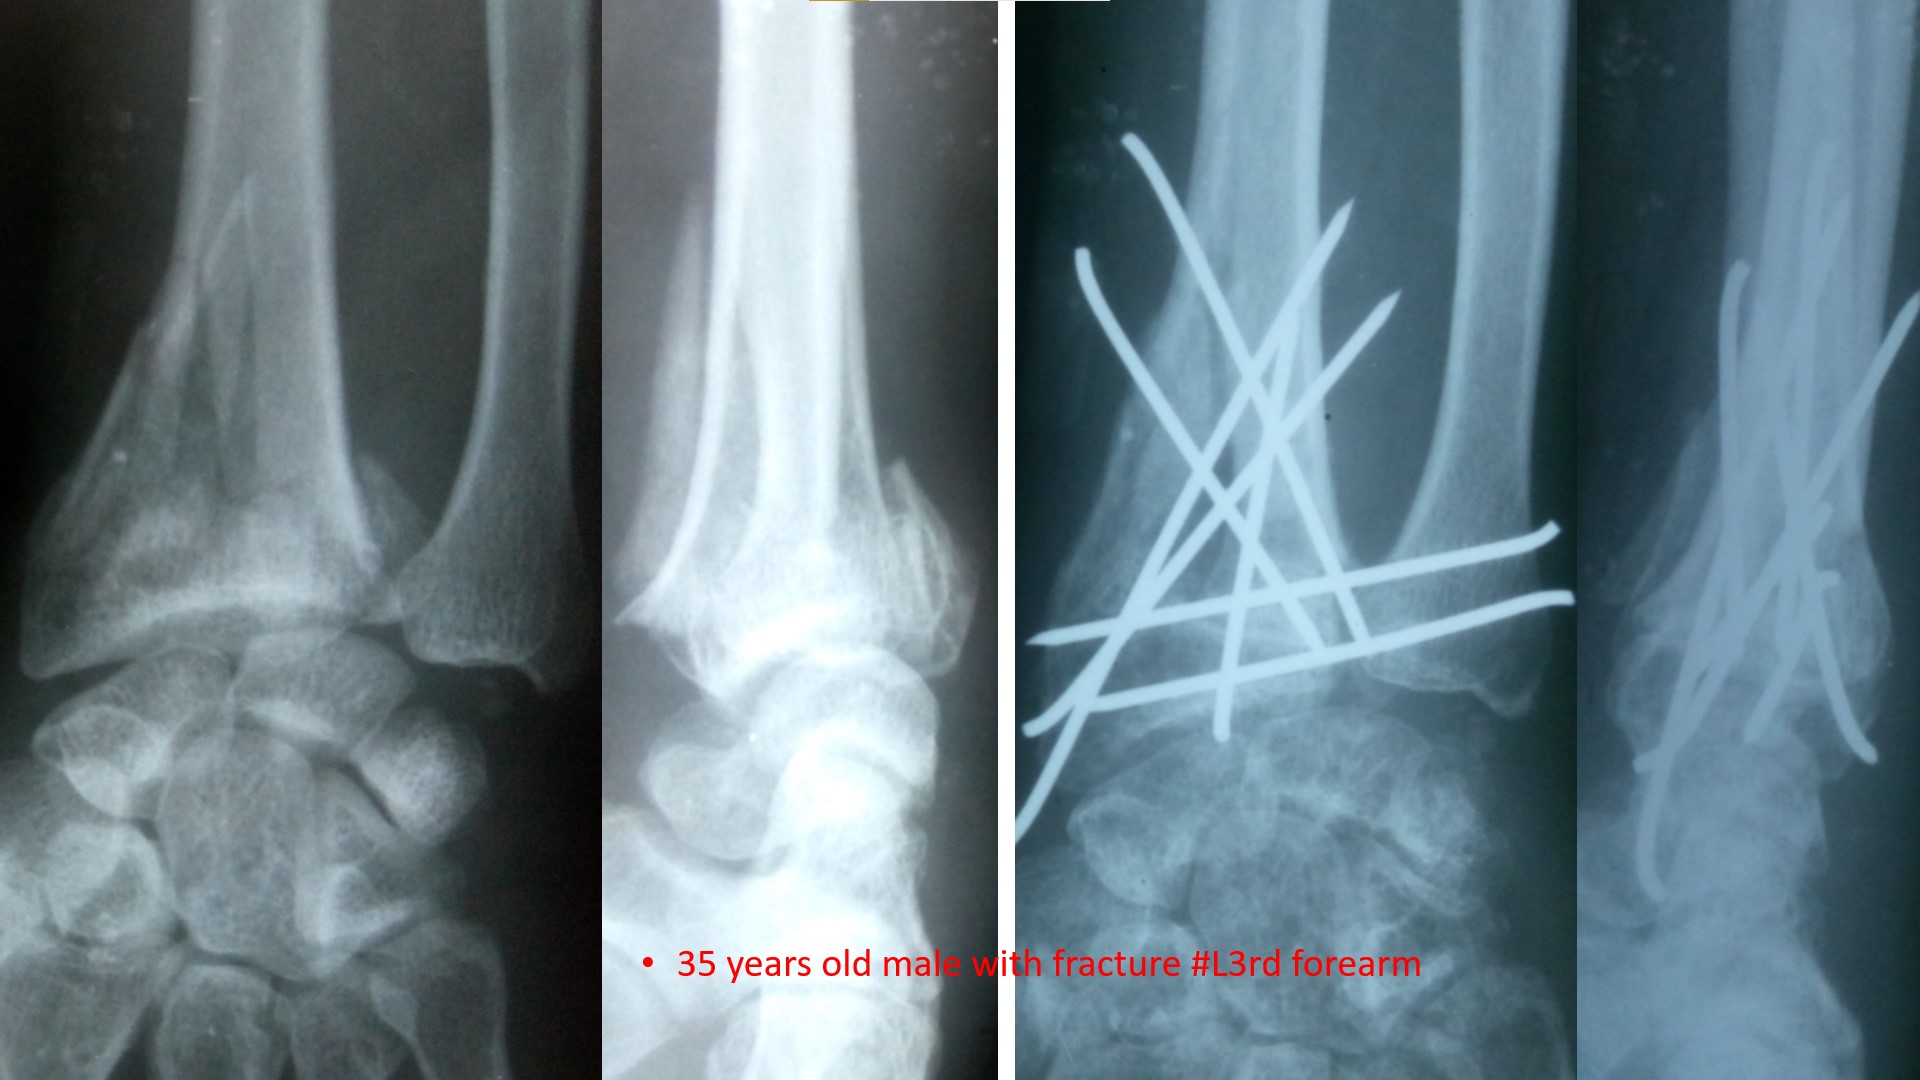

FRACTURE LOWER 3RD FOREARM